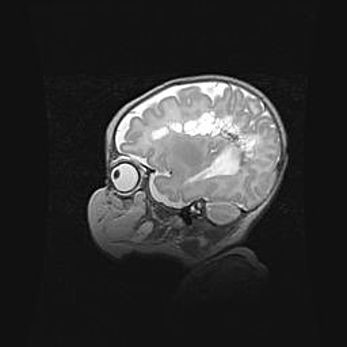

Наружная гидроцефалия с возможной атрофией височных областей.

Возраст: 28 дней

Вес: 3670 г

Пол: мужской

Окружность головы: 38 см

Срок гестации: 40 недель

Гидроцефалия головного мозга у новорожденных – это заболевание, которое характеризуется скоплением избыточного количества спинномозговой жидкости в желудочковой системе головного мозга в результате затруднения её перемещения от места выработки к месту поглощения в кровеносную систему или вследствие нарушения абсорбции. При открытой наружной форме гидроцефалии у новорожденных расширяются и переполняются субарахноидные пространства.

При нормотензивных  формах,  которые,  как  правило,  являются  следствием  перенесенных ишемических  повреждений  паренхимы  мозга,  возможно  сочетание микроцефалии  с нормотензивной гидроцефалией. В основе данных изменений лежит атрофия больших полушарий с преимущественной  локализацией  в  лобно-височных  областях.